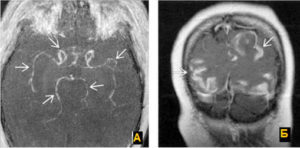

Церебральный васкулит. Заболевание, вызванное воспалительным процессом в стенке мозговых сосудов. Возникает в основном вторично. Проявления вариабельны: энцефалопатия, парезы, психические нарушения, эпилептические приступы, обмороки, зрительные расстройства, тугоухость, атаксия.

Диагностика опирается на клинические сведения, данные неврологического статуса, результаты МРТ, церебральной ангиографии, исследования ликвора, биохимии крови. Лечение проводится дифференцированно в соответствии с этиологией и клиническими особенностями.

Может включать кортикостероиды, цитостатики, сосудистые препараты, ноотропы, симптоматические средства.

Церебральный васкулит (ЦВ) возникает преимущественно в структуре системных васкулитов или на фоне инфекций, ревматических заболеваний, онкопатологии, интоксикаций. Термин «васкулит» означает воспалительное поражение сосудистой стенки. Изолированный васкулит мозговых сосудов относится к редким формам.